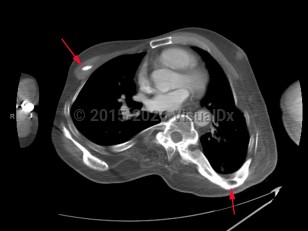

Progressive osseous heteroplasia in Child

A rare autosomal dominant disorder. Initial manifestation is primary osteoma cutis, a condition of true bone formation within the skin, usually beginning in infancy. Lesions are tender and may ulcerate. Progresses to involve bone formation in deep connective tissue and skeletal muscle. May result in restricted movement and abnormal growth.